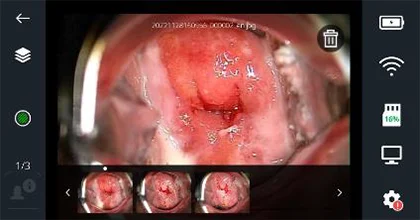

Зураг 9а - Үзлэгийн үеийн дэлгэцийн харагдац

Зүүн доод талд байгаа цомгийн товчлуур дээр дарахад та зургийн цомгийн дэлгэцийг харах болно. Зургийн цомгийн дэлгэцийн голд хамгийн сүүлд авсан зураг, доод мөрөнд өмнөх зургийн жагсаалт, хоёр талдаа хажуугийн цэс харагдана. Доод зургийн жагсаалтад зургуудыг авсан цагийн дарааллаар жагсааж харуулдаг. Дараагийн зургуудыг харахын тулд гүйлгэж харна уу! Цагаан өнгийн цэг нь таны одоо харж байгаа зургийг илэрхийлнэ.

Зураг 12 - Цомгийн дэлгэцийн харагдац